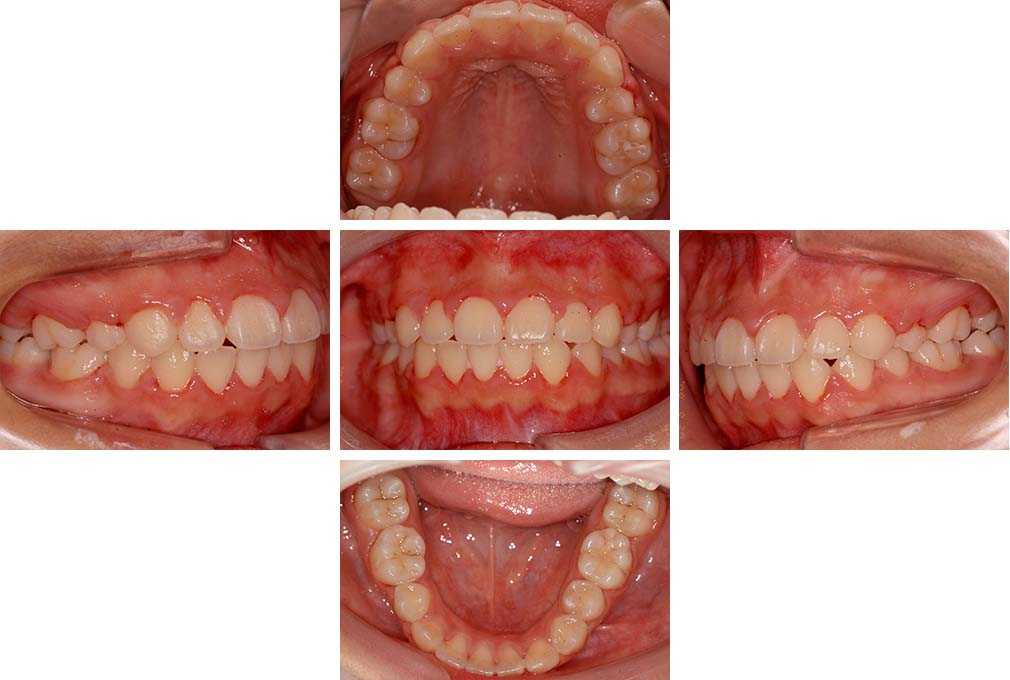

CASE:02

下顎前歯部叢生、小臼歯4歯先天欠損

初診時年齢 14歳3か月

性別 女性

治療費の目安 70万円(治療開始時)

上顎左右側小臼歯3歯、下顎左側第二小臼歯の先天欠損と下顎前歯の叢生を主訴として近隣一般歯科から紹介来院した。

上顎左側第一、第二小臼歯、右側第一小臼歯、下顎左側第二小臼歯が先天欠損であったが、左上第二乳臼歯の根の吸収がほぼ無いことから、これを残すこととして、下顎左側乳臼歯と、右側第二小臼歯を抜歯していただきマルチブラケット装置を使用して動的治療を行った。矯正用ゴムなどの協力状態も良く2年0カ月(調整来院19回)で装置を撤去し保定へ移行した。動的治療終了13年2カ月での来院時には下顎左右側智歯が萌出していたが、垂直的に萌出していたため抜歯は行っていない。

治療前

14歳3か月

治療後

動的治療期間2年0カ月

16歳7か月

13年経過

動的治療終了後13年2カ月

30歳0か月